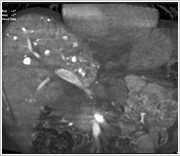

こちらの検査室では、立体的な血管像やCTのような画像を作成することができ、診断や治療の確認に利用していきます。

こちらの検査室では、立体的な血管像やCTのような画像を作成することができ、診断や治療の確認に利用していきます。

CTのような断層の画像を表示することもできます。